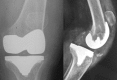

Today, total knee arthroplasty (TKA) is one the most commonly performed surgeries worldwide. The purpose of this article is to review the appearance of normal post-TKA roentgenographs and describe the correct sequence for their interpretation. It is unwise to depend solely on patients' symptoms when diagnosing TKA complications because serial radiographs can foresee failures well before they manifest clinically. Ideal post-TKA radiographs comprise whole lower extremity anteroposterior and lateral views taken under weight bearing conditions along with a skyline view of the patellofemoral joint. Among other things, weight bearing exposes the true alignment, ligamentous laxity and polyethylene wear. On the basis of follow-up of our TKA cases, we have drawn up a protocol for assessing postoperative X-ray films after TKAs. Following the proposed sequence, surgeon can easily decide how to proceed with follow-up and foresee complications. Careful interpretation of postoperative radiographs after TKA is essential to careful monitoring of patients and implant survival.